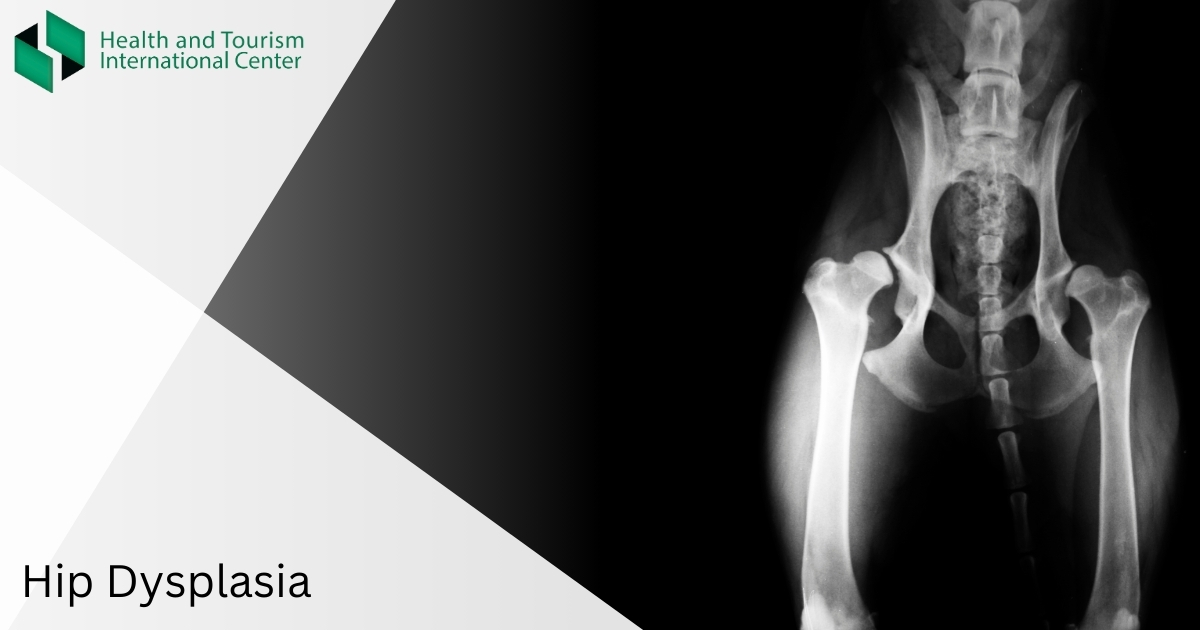

Hip dysplasia means that the bone in the hip joint has not fitted together properly. Hip dysplasia is an underdevelopment of the components of the joint – the result of abnormal development and weakness of the connective tissue.